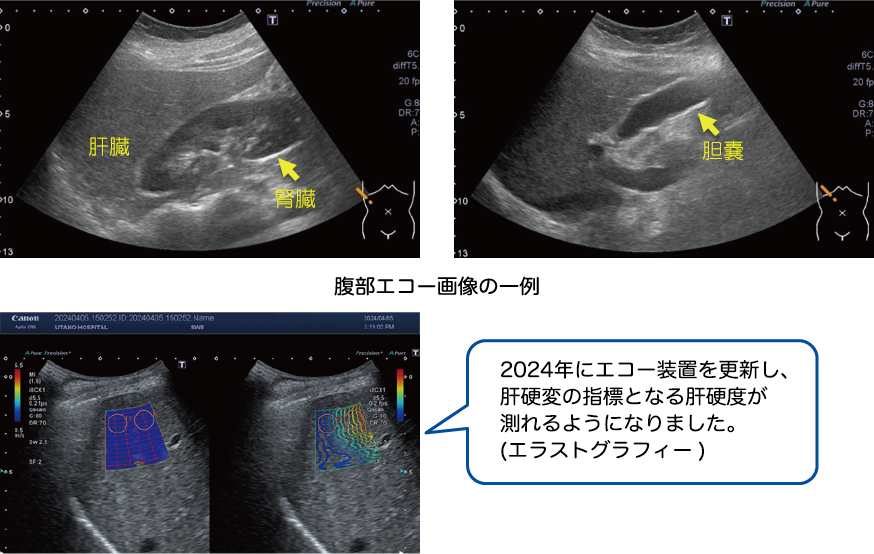

腹部超音波検査(腹部エコー)

お腹にゼリーを付けたプローブ(超音波発信機)を当て、主に肝臓・胆嚢・膵臓・腎臓・脾臓等の腹部の臓器の状態を調べます。

各臓器の形態や腫瘤の有無、びまん性疾患の診断に役立ちます。